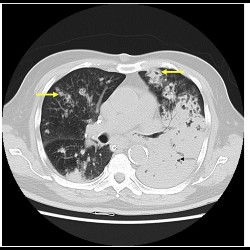

CT in detection and diagnosis of thoracic conditions in symptomatic HIV patients

CT in detection and diagnosis of thoracic conditions in symptomatic HIV patients

CT in detection and diagnosis of thoracic conditions in symptomatic HIV patients

CT in detection and diagnosis of thoracic conditions in symptomatic HIV patients

Pulmonary nocardiosis: Under-diagnosed respiratory opportunistic infection

Pulmonary nocardiosis: Under-diagnosed respiratory opportunistic infection - A Case report

Pulmonary nocardiosis: Under-diagnosed respiratory opportunistic infection

Pulmonary nocardiosis: Under-diagnosed respiratory opportunistic infection - A Case report